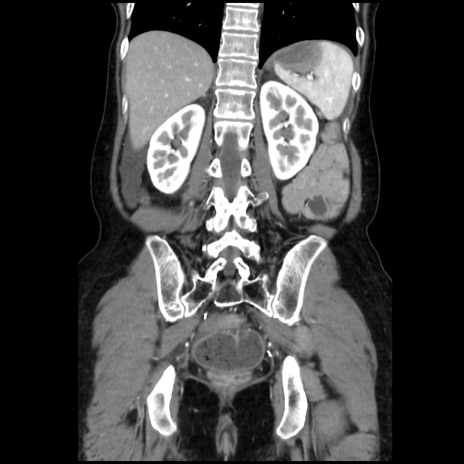

症例32(冠状断像)

【症例】40歳代 女性

【主訴】上腹部痛、嘔気・嘔吐

【現病歴】約9時間前頃から急に上腹部痛、嘔気、嘔吐が出現。改善しないため救急要請。

【既往歴】子宮頚癌(広汎子宮全摘術、放射線療法)、腸閉塞

【身体所見】腹部:平坦、軟、腸雑音亢進、上腹部を中心に腹部全体に圧痛あり。

【データ】WBC 8400、CRP 0.03